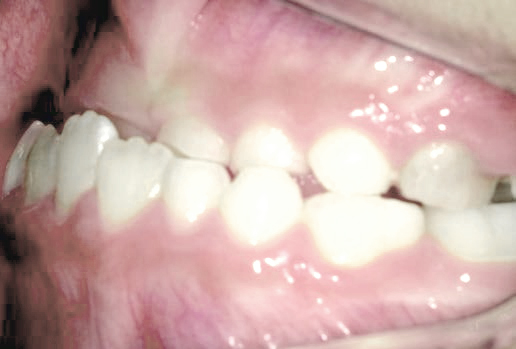

八重歯になっちゃった…歯が入る隙間がないけど、永久歯は抜きたくない!

Aさん (矯正開始時:9歳)

Before

After

すっきりしたお顔立ちの女の子ですが、外側から八重歯が生えてきてしまいました。

治療を終えて

マイオブレイスとBWS装置を使い、あごの骨や歯並びの形を整えながら、鼻呼吸や正しい飲み込み方も身に付けることができました。

お口の悪いクセは改善され、お子さん自身の力でしっかりとしたかみ合わせができるようになりました。ご希望通り永久歯を抜く必要はありませんでした。

主訴・治療内容 他院で「永久歯を抜いて矯正」をすすめられたが抜歯に抵抗があり「永久歯を抜かずに、あごの骨から整えてくれる」と口コミを見て当院を選んでくださいました。

治療期間 2年

費用 495,000円(税込)